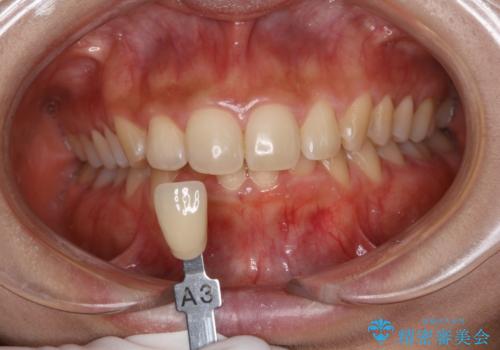

- 1か月後に結婚式があるため、歯を白くしたいとのことでした。

オフィスホワイトニング(TION Whitening・処置前クリーニング込み)コースを行いました。

ホワイトニング後は、ホワイトバンドや白い斑点がでることがあります。

その場合、追加でオフィスホワイトニングを行うことや、ホームホワイトニングの併用を行うことで、均一な白さに近づけることができます。